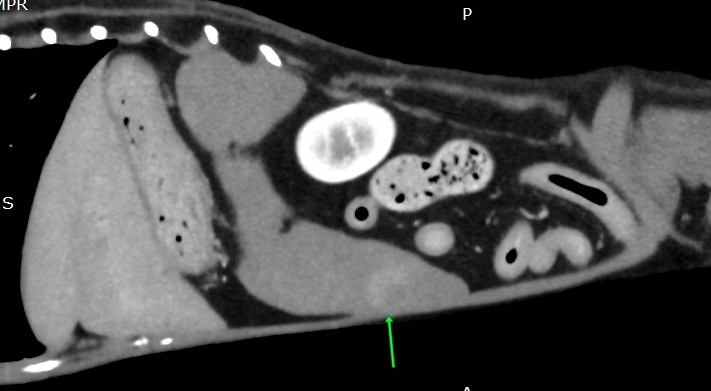

数日後CT検査にて、

やはり、ある

CT検査診断:脾臓に結節、胆泥症

この脾臓の結節、不気味です